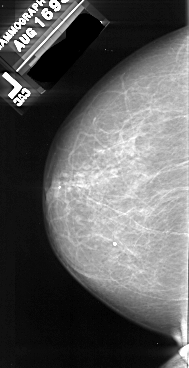

A_1085_1.LEFT_MLO

LEFT_MLO LINES 5986 PIXELS_PER_LINE 3151 BITS_PER_PIXEL 16 RESOLUTION 42 NON_OVERLAY